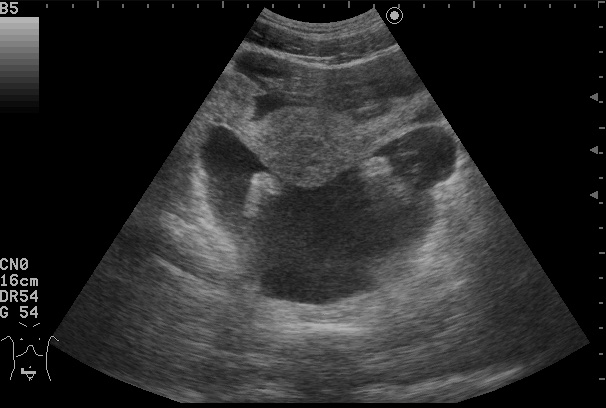

Где ЭТО?

Где все ЭТО, характерное для асцита?

3.55.jpg

x180502--093036_20180502_Adult-_Abdomen_0028.JPG

AAGD.jpg